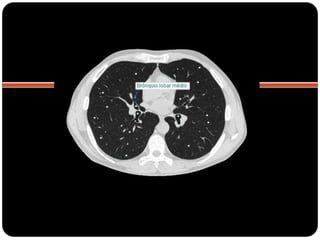

 TC janela de parênquima

 Brônquios principais originam-se da traquéia

na carina;

 Brônquio direito: ângulo mais obtuso com o

 Direito(2,2cm) mais curto que o

esquerdo(5cm);